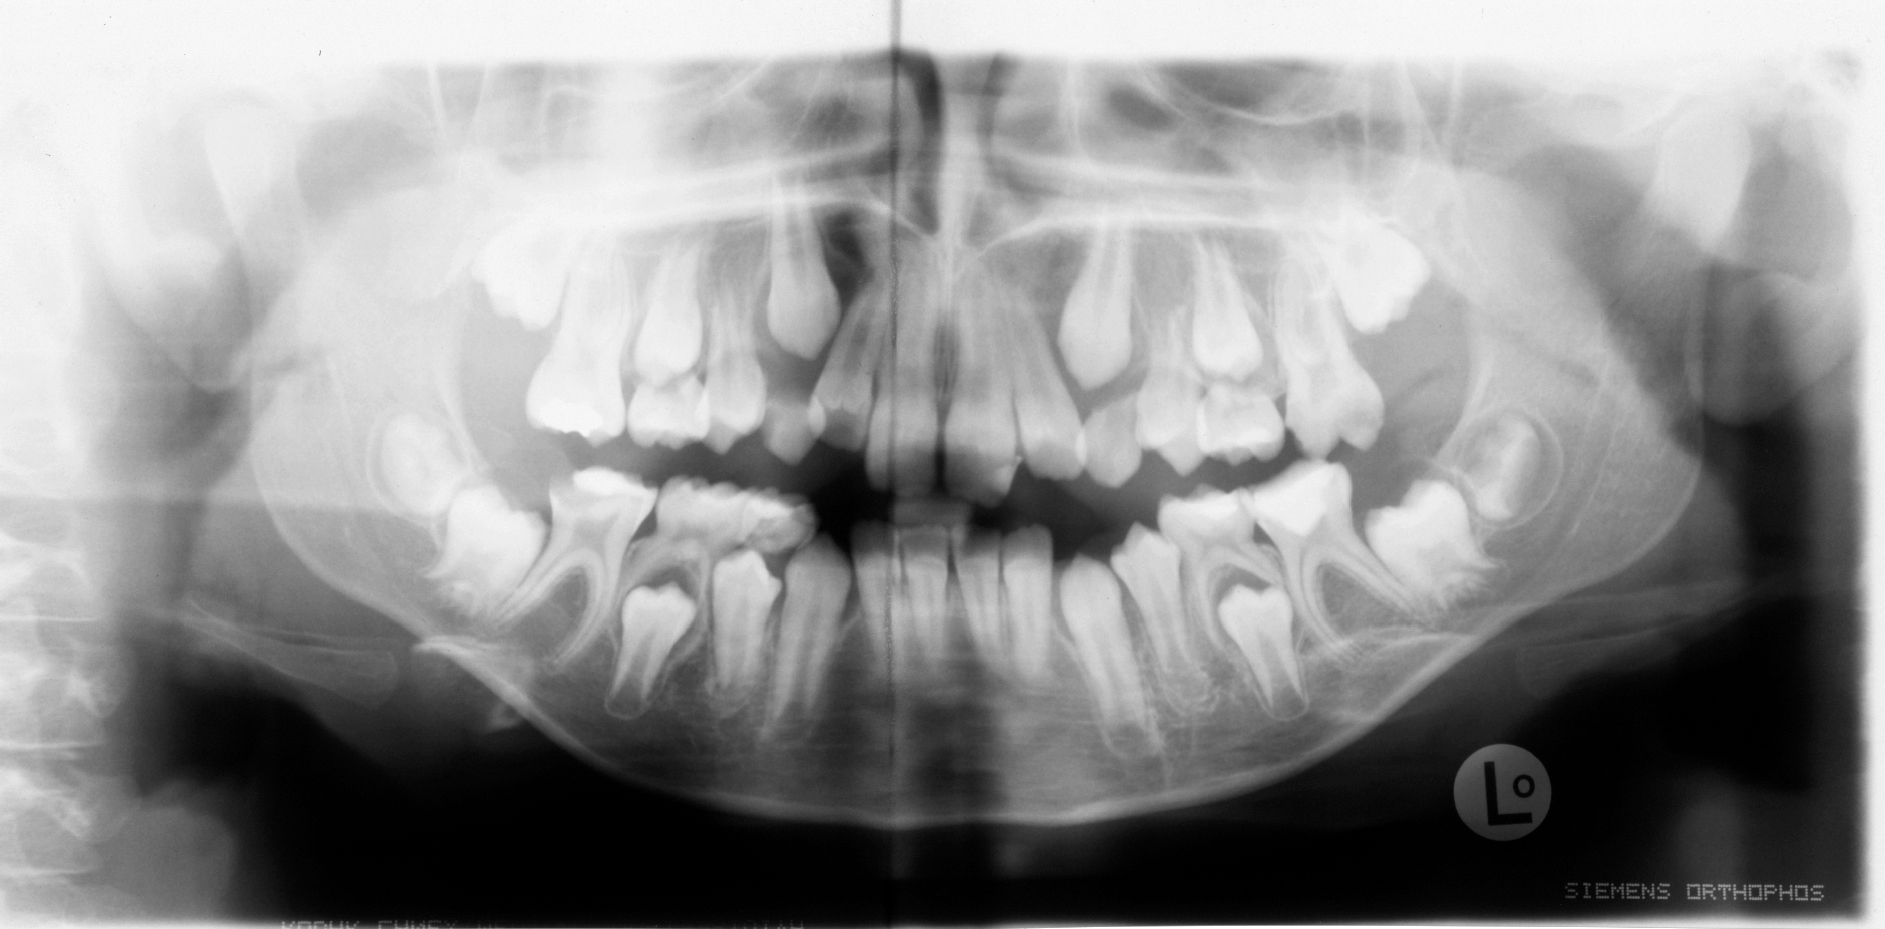

Allerdings sollte vor der geplanten Extraktion eines Sechsjahrmolaren eine radiologische und kieferorthopädische Beurteilung der Gebisssituation erfolgen [Brusevold et al., 2022], um die Anlage der bleibenden Zahnkeime zu überprüfen und mögliche Dysgnathien zu diagnostizieren [Ashley and Noar, 2019]. Zusätzlich sollte der optimale Zeitpunkt für eine geplante Extraktion gewählt werden [Lygidakis et al., 2022].

Auch wenn ein Alter von acht bis zehn Jahren als geeigneter Zeitpunkt für die Extraktion eines Sechsjahrmolaren gilt, ist der spontane Lückenschluss nicht immer gewährleistet [Ashley und Noar, 2019]. Insbesondere bei der Extraktion von Sechsjahrmolaren im Unterkiefer gilt der spontane Lückenschluss als weniger wahrscheinlich als im Oberkiefer [Brusevold et al., 2022].

In Anbetracht der Tatsache, dass bei ausbleibendem spontanen Lückenschluss nach der Zahnextraktion eine kieferorthopädische Behandlung indiziert sein kann [Jälevik und Möller, 2007], ist eine sorgfältige Aufklärung und die Berücksichtigung der Wünsche der Kinder und deren Sorgeberechtigten wichtig, um im Einzelfall die bestmögliche Therapieentscheidung zu treffen.